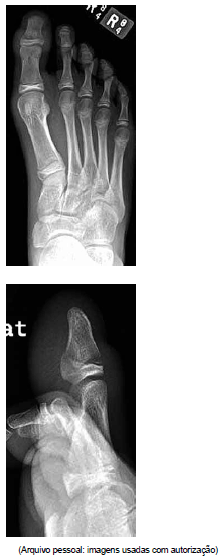

Menino de 13 anos sofreu fratura do dedo do pé, e optou-se por tratamento conservador. Alguns dias após, ele evoluiu com edema de partes moles e hematoma subungueal.

A radiografia realizada é mostrada a seguir.